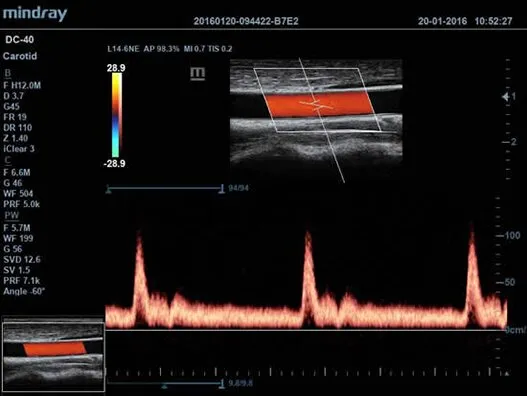

Клинические изображения

Авто IMT (толщина интима-медиа)

Автоматическое измерение толщины задней и передней стенок, дающее точные сведения о состоянии сонной артерии.

| L14-6NE | Высокочастотный линейный датчик для поверхностных органов и структур, периферических сосудов, неонатологии и педиатрии |